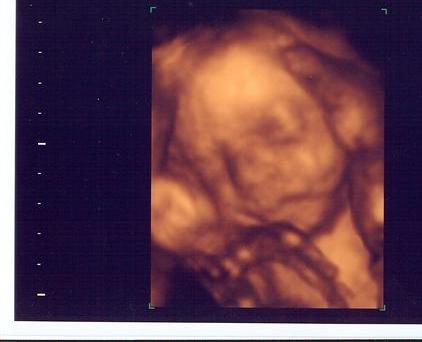

Just got back from 3D sonogram at Impact!!

Here she is!!

Image Attachment(s):